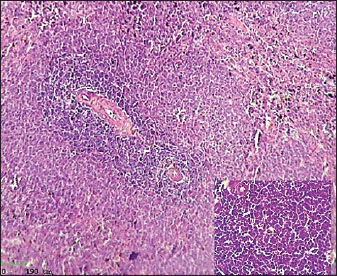

Histological analysis of spleen

Histological examination of the splenic tissue of rats treated with L-arginine showed notable pathological alterations. These included: Congestion of blood vessels within both the red and white pulp and lymphoid hyperplasia in the white pulp, indicating increased proliferation of lymphoid cells, suggestive of immune stimulation or chronic inflammation (Fig. 4). In contrast, the spleen from control male rats exhibited normal histological architecture. The white pulp and red pulp regions were clearly distinguishable. Central arteries and blood vessels appeared unremarkable, and no signs of congestion, inflammation, or hyperplasia were observed. The lymphoid follicles within the white pulp were of normal size and density (Fig. 3)

Fig. 3. Histological section of male rat spleen of control group, stained with Hematoxylin and Eosin (H&E), showing villus structure at 10x magnification using light microscopy.

Fig. 4. Histological section of male rat spleen treated with L-arginine, stained with Hematoxylin and Eosin (H&E), showing villus structure at 10x magnification using light microscopy.

Lymphoid hyperplasia of the spleen is when there are more lymphocytes than usual. It usually happens because of an inflammatory or immune response. This finding usually means that the immune system is working harder or longer in the spleen, which shows that the immune system is still controlling the body as a whole. This kind of hypertrophy is a sign of an active immune system or long-term inflammation (Hobbie et al., 2024).

During enteritis, the spleen is an important part of the immune system because it filters the blood and is where immune cells first become active. According to Mebius and Kraal (2005). There is a white pulp in the spleen that helps activate and multiply lymphocytes. This makes it possible for adaptive immune reactions to work together. In the context of enteritis, inflammation in the intestines can cause microbial products and inflammatory chemicals to move into the bloodstream. The spleen is very important for getting rid of these substances and keeping the defense system working as a whole. This shows how important the spleen is for keeping the immune system in balance during times of inflammation in the gut. It also helps control inflammation outside of the gut and stops infections from spreading.